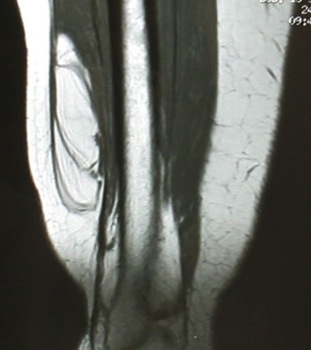

Intra-muscular lipoma

Deep to fascia

Marginal resection

Recurrence uncommon